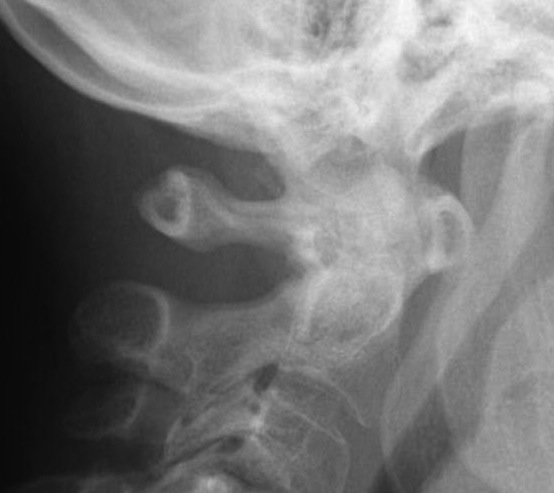

Subaxial Subluxation (SAS)

Definition

Anterior subluxation of one vertebral body on another

Results in spinal stenosis

Diagnosis

A. Instability on Flexion / Extension views

- > 3mm

- > 11o

Anterior subluxation of C3 on C4

B. Space available for cord / SAC

- subaxial canal diameter on lateral

- < 13 mm high incidence neurology

Pathology

Facet erosions / ligament incompetence

May see at multiple levels with stepladder type deformity & kyphosis

Can occur beneath previous cervical fusions including C1/C2